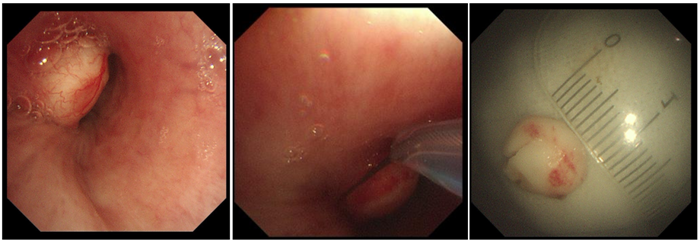

2月15日,由于世倫副院長親自操作,在狄紅紅主治醫(yī)師、田忠敏護士長協助下,成功為患者行高頻電套扎切除結節(jié)狀白色腫物。

患者左主支氣管遠端見結節(jié)狀白色腫物,表面上有少許表淺血管顯露,基底較寬,堵塞管腔約70%,予以高頻電套扎切除,少許出血,給與局部噴灑腎上腺素溶液止血,標本送病理。2月16日病理結果示:肺錯構瘤。患者于2月16日出院,醫(yī)護人員就復診問題給予其詳細的指導。